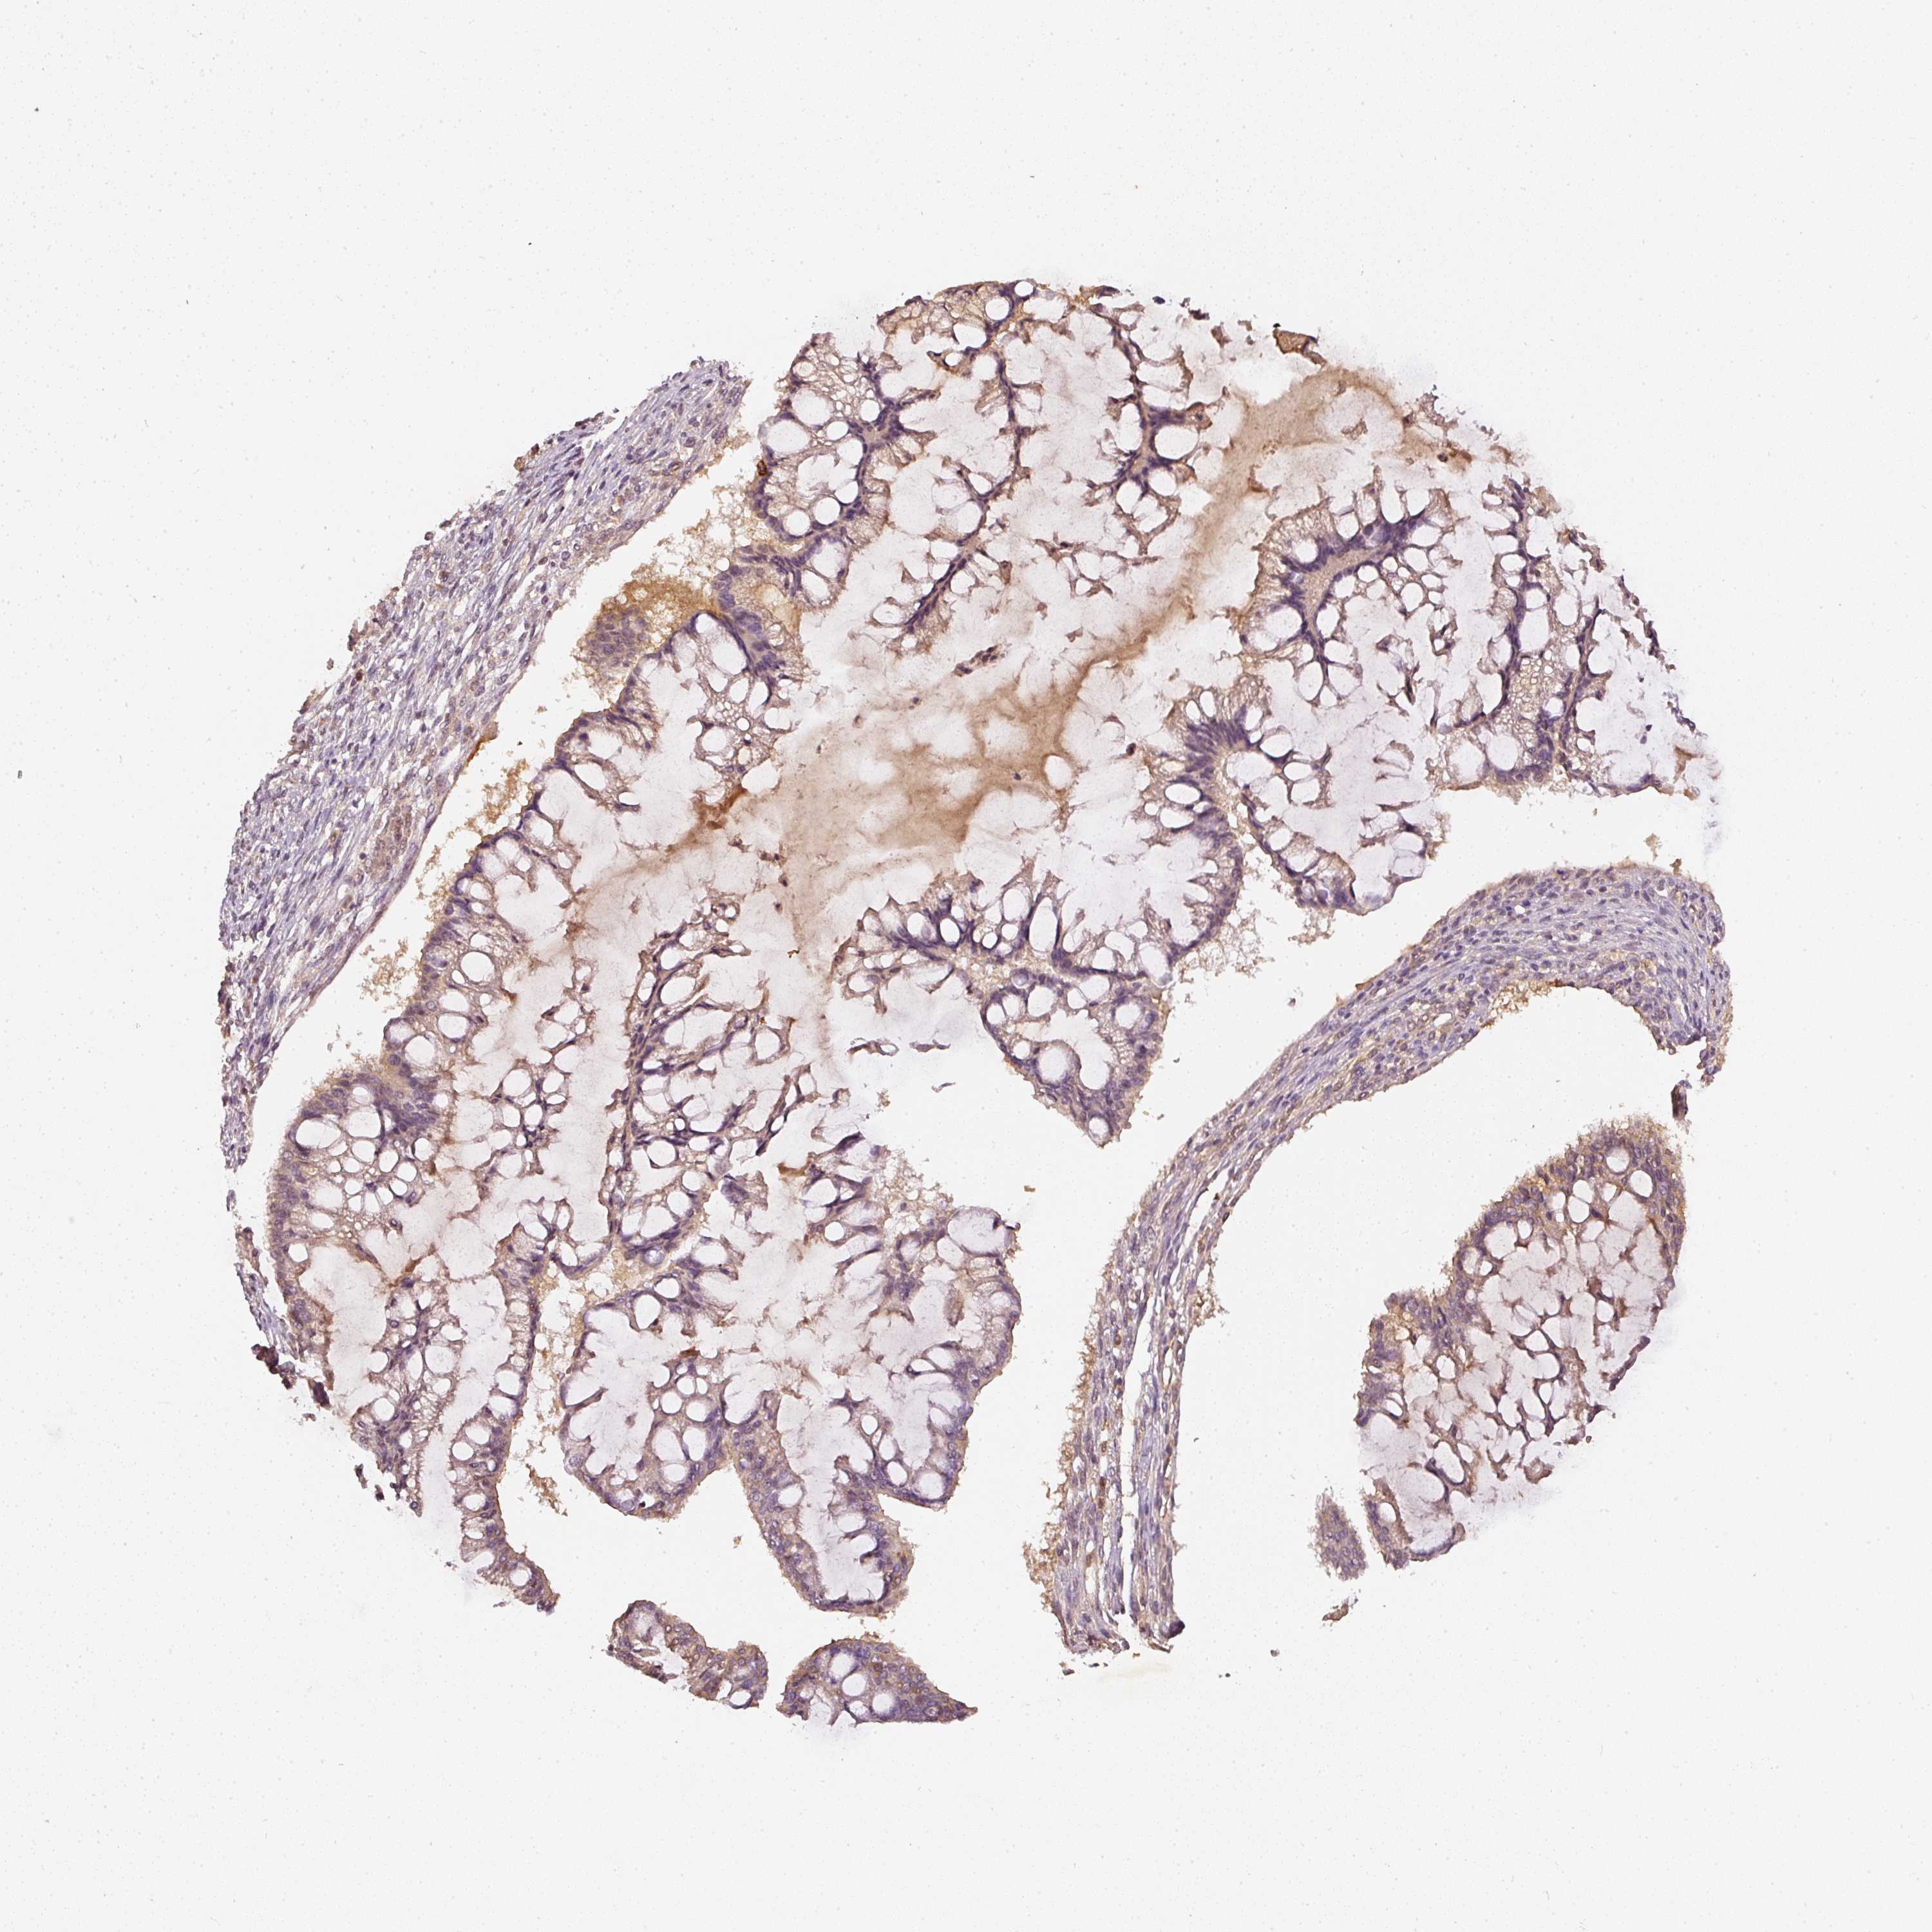

OVARIAN CANCER - Protein expressioni

A mouse-over function shows sample information and annotation data. Click on an image to view it in a full screen mode. Samples can be filtered based on level of antibody staining by selecting one or several of the following categories: high, medium, low and not detected. The assay and annotation is described here.

Note that samples used for immunohistochemistry by the Human Protein Atlas do not correspond to samples in the TCGA dataset.

Antibody stainingi

Antibody staining in the annotated cell types in the current human tissue is reported as not detected, low, medium, or high, based on conventional immunohistochemistry profiling in selected tissues. This score is based on the combination of the staining intensity and fraction of stained cells.

Each image is clickable and will lead to virtual microscopy that enables deeper exploration of all samples and also displays staining intensity scores, fraction scores and subcellular localization as well as patient and tissue information for each sample.

Antibody HPA018849

Antibody HPA019536

Antibody CAB033987

Staining

High

Medium

Low

Not detected

Cystadenocarcinoma, serous, NOS

Carcinoma, endometroid

Cystadenocarcinoma, mucinous, NOS

Carcinoma, NOS